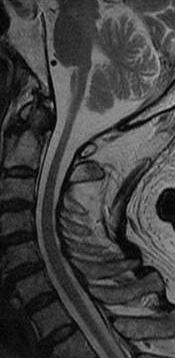

延髄・脊髄優位型アレキサンダー病ではMRI検査を行なうと、延髄や上位頸髄が顕著に細くなっている(萎縮している)という特徴的な所見がみられます。大脳優位型のアレキサンダー病とは異なり、大脳の前頭部には顕著な異常はみられません。